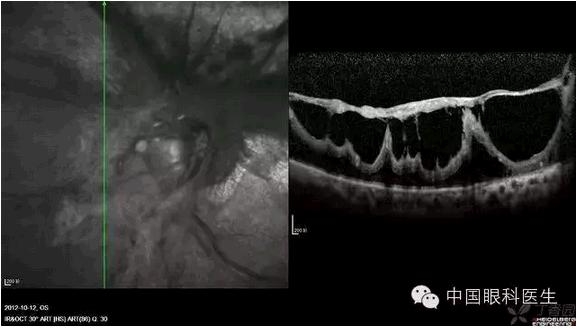

视网膜劈裂 OCT图

增殖膜